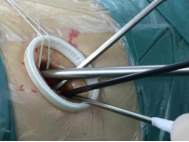

較兩孔、多孔胸腔鏡手術或傳統手術,單孔手術具有創傷更小、出血更少、術后疼痛更輕、瘢痕小、切口更加美觀、術后恢復快、住院時間短等優勢。但手術中所有器械(包括觀察鏡、吸引器、電凝鉤、切割閉合器、雙關節等各種操作器械)都要是從一個小“孔”進入,器械之間的互相干擾,同時器械與觀察鏡幾乎平行,視野非常狹窄,手術難度明顯,增加極其考驗醫生的技術。

器械進入小孔。